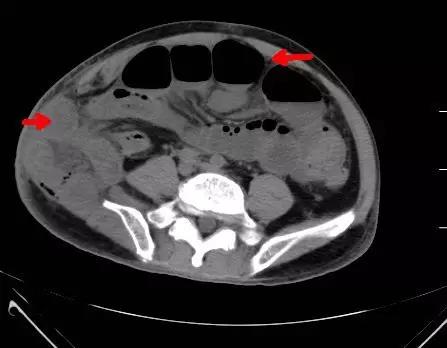

小肠疝出右侧腹壁皮下,合并肠梗阻

右侧骨盆粉碎性骨折